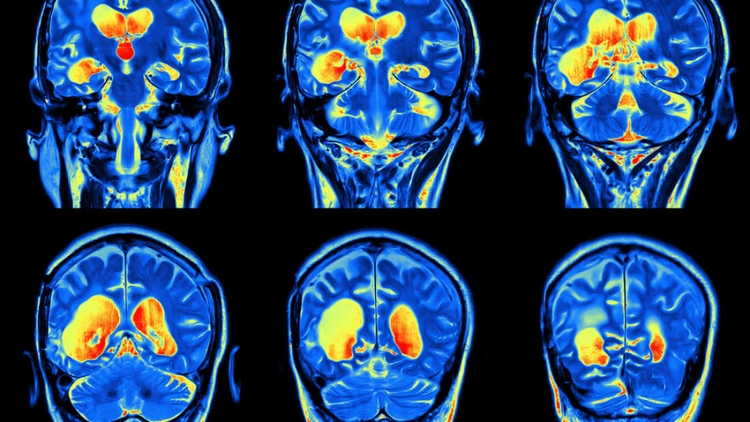

脑部的核磁共振扫描(不是来自这项研究)。

人类中间(与奖赏有关,OFC13)和侧面(与奖赏无关,OFC47/12)眼窝前额脑皮层网络,显示在忧郁症病患不同的功能连接。University of Warwick

在中国,以高精密度的核磁共振(MRI)扫描了909位病患的脑部后,这些研究人员达成这项结论。在这些病患中,421位被诊断出严重的忧郁症,其他的488位则是控制的对象。

这个成像技术能够显示出人类脑部受到忧郁症影响不同区块之间连接的活动,那就是中间和侧面眼窝前额脑皮层。侧面眼窝前额脑皮层与没有奖赏有关联,在忧郁症群的病患中,显示出相当强烈的连接。